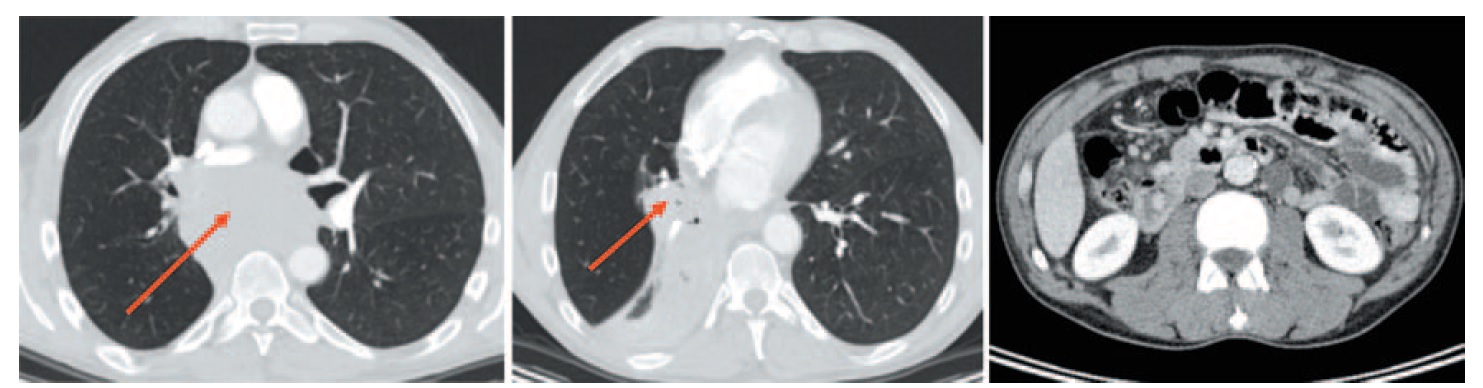

С целью стадирования заболевания в июне 2017 г. выполнена МСКТ головного мозга, органов грудной клетки, брюшной полости и малого таза (рис. 2). В области корня правого легкого с переходом на заднее средостение выявлен опухолевый конгломерат, состоящий из опухолевого узла без четких контуров и увеличенных сливающихся бронхолегочных, бифуркационных, параэзофагеальных лимфоузлов. Общие размеры конгломерата лимфоузлов составили 88×57 мм. Промежуточный, нижнезональный, среднедолевой бронх прослеживались фрагментарно. Также выявлен ателектаз нижней и средней долей правого легкого. Отмечено распространение процесса на правый главный и верхнедолевой бронх, область бифуркации трахеи. Конгломерат вызывал компрессию левого главного бронха и левого предсердия. Выявлены компрессия и признаки опухолевой инвазии правой легочной артерии (оттеснение и сужение на протяжении 24 мм). Также визуализированы отдельно расположенные неувеличенные внутригрудные лимфоузлы левой бронхолегочной и паратрахеальной группы и параэзофагеальный лимфоузел справа размером 20×18 мм. В области брюшины определялись неорганные узловые образования, накапливающие контрастный препарат, размерами до 8 мм. При МСКТ головного мозга выявлена венозная ангиома в левой лобной области.

Рис. 2. МСКТ до начала терапии (июнь 2017 г.). Центральный рак правого легкого с поражением правого нижнезонального бронха с переходом на среднедолевой, главный бронхи. Метастазы во внутригрудных лимфоузлах, нельзя исключить переход процесса на область бифуркации трахеи, правую легочную артерию. Неорганные узловые образования в брюшной полости – канцероматоз брюшины. / Fig. 2. Multispiral computed tomography (MCT) before the therapy (June 2017). Centrally located right lung cancer with the lesion on the right lower lobe bronchus with the damage of the middle lobe bronchus and the primary bronchi. Intrathoracic lymph nodes metastases, it is not inconceivable that the damage took the area of bifurcation of the trachea, the right pulmonary artery. Inorganic abdominal mass – peritoneal carcinomatosis.

На основании результатов обследования пациенту был поставлен диагноз: центральный мелкоклеточный рак правого легкого, метастазы в лимфатических узлах средостения. Канцероматоз. сT2bN2M1 – IV стадия.